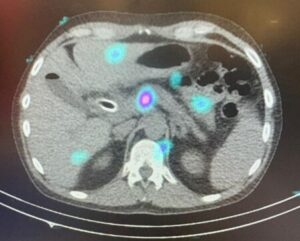

Primeiro tratamento com o dispositivo OncoSil™ realizado em Portugal

Um marco histórico na luta contra o cancro do pâncreas, em colaboração com o IPO-Porto e a OncoSil Medical

Pela primeira vez em Portugal, um doente com cancro do pâncreas foi tratado com sucesso com o dispositivo OncoSil™, no Instituto Português de Oncologia do Porto (IPO-Porto), em parceria com a OncoSil Medical.

Este avanço representa um importante passo na introdução de terapias inovadoras que oferecem novas opções de tratamento para uma patologia de prognóstico difícil.